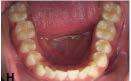

Tras 3 meses después de la carga inmediata de los implantes anteroinferiores, y 3 meses tras la carga de los implantes del cuarto cuadrante, se confecciona la prótesis definitiva inferior para ambos sectores. Esta se realiza en metal-cerámica, cementada, al igual que la superior, utilizando pilares ceramizados en las zonas estéticas (Figuras 19–21).

La paciente continúa bajo seguimiento periodontal. A los 5 años se observa estabilidad clínica del tratamiento (Figuras 22–24), sin recesiones gingivales ni pérdida ósea asociada en las imágenes clínicas y radiográficas.

Un año más tarde, al finalizar el periodo de seguimiento (24 años), las fotografías intraorales evidenciaron ligeras alteraciones de los tejidos blandos, con pequeñas troneras abiertas,

más evidentes en los dientes naturales conservados que en las restauraciones implantosoportadas. A pesar de estos cambios, el resultado global se consideró satisfactorio desde el punto de vista funcional y estético, especialmente en comparación con la situación clínica y radiográfica inicial previa al tratamiento (Figuras 26–31).